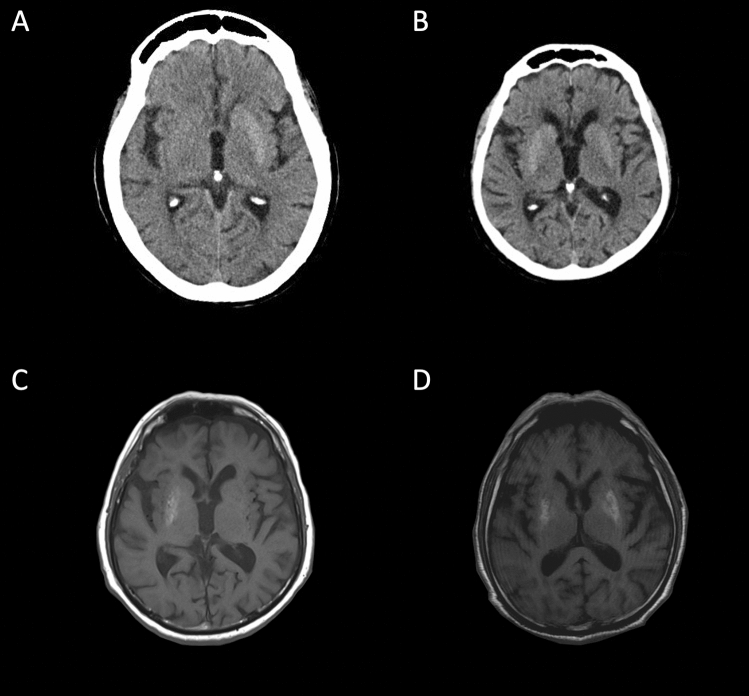

Typical neuroradiological changes are striatal hyperdensity on CT scan and hyperintensity on T1-weighted MRI (Fig. 2). Isolated contralateral putamen is the most frequent striatal abnormality, followed by simultaneous involvement of contralateral caudate nucleus and putamen with constant sparing of the internal capsule [2, 7, 68]. Involvement of all three striatal components (caudate nucleus, putamen and globus pallidus) is possible [2]. However, the association between neuroimaging changes and symptoms varies widely. Although the limbs are more frequently clinically involved (in order of frequency arm-leg, arm-leg-face and isolated arm), two cases of isolated facial hemichorea with oral dyskinesia and grimacing are also reported [73, 74].

Fig. 2.

Typical neuroimaging of diabetic striatopathy. A, B Axial CT scan: contralateral caudate nucleus and putamen (A) and bilateral striatal hyperdensity (B). C, D Axial T1-weighted MR image: contralateral (C) and bilateral pallidal-putaminal (D) hyperintensity can be observed